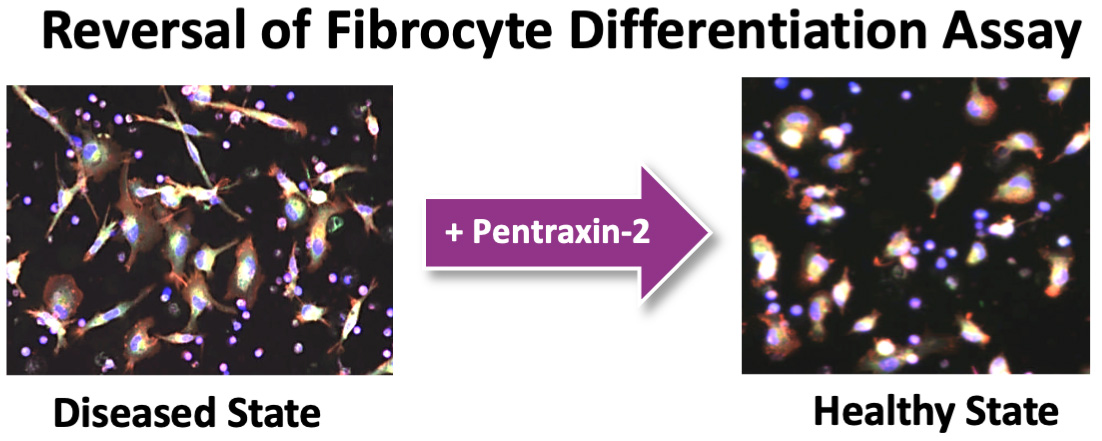

•In-licensed a program (Target Epsilon) that emerged from our fibrosis collaboration with Bayer that represents a novel approach to treating fibrotic diseases with compelling early data